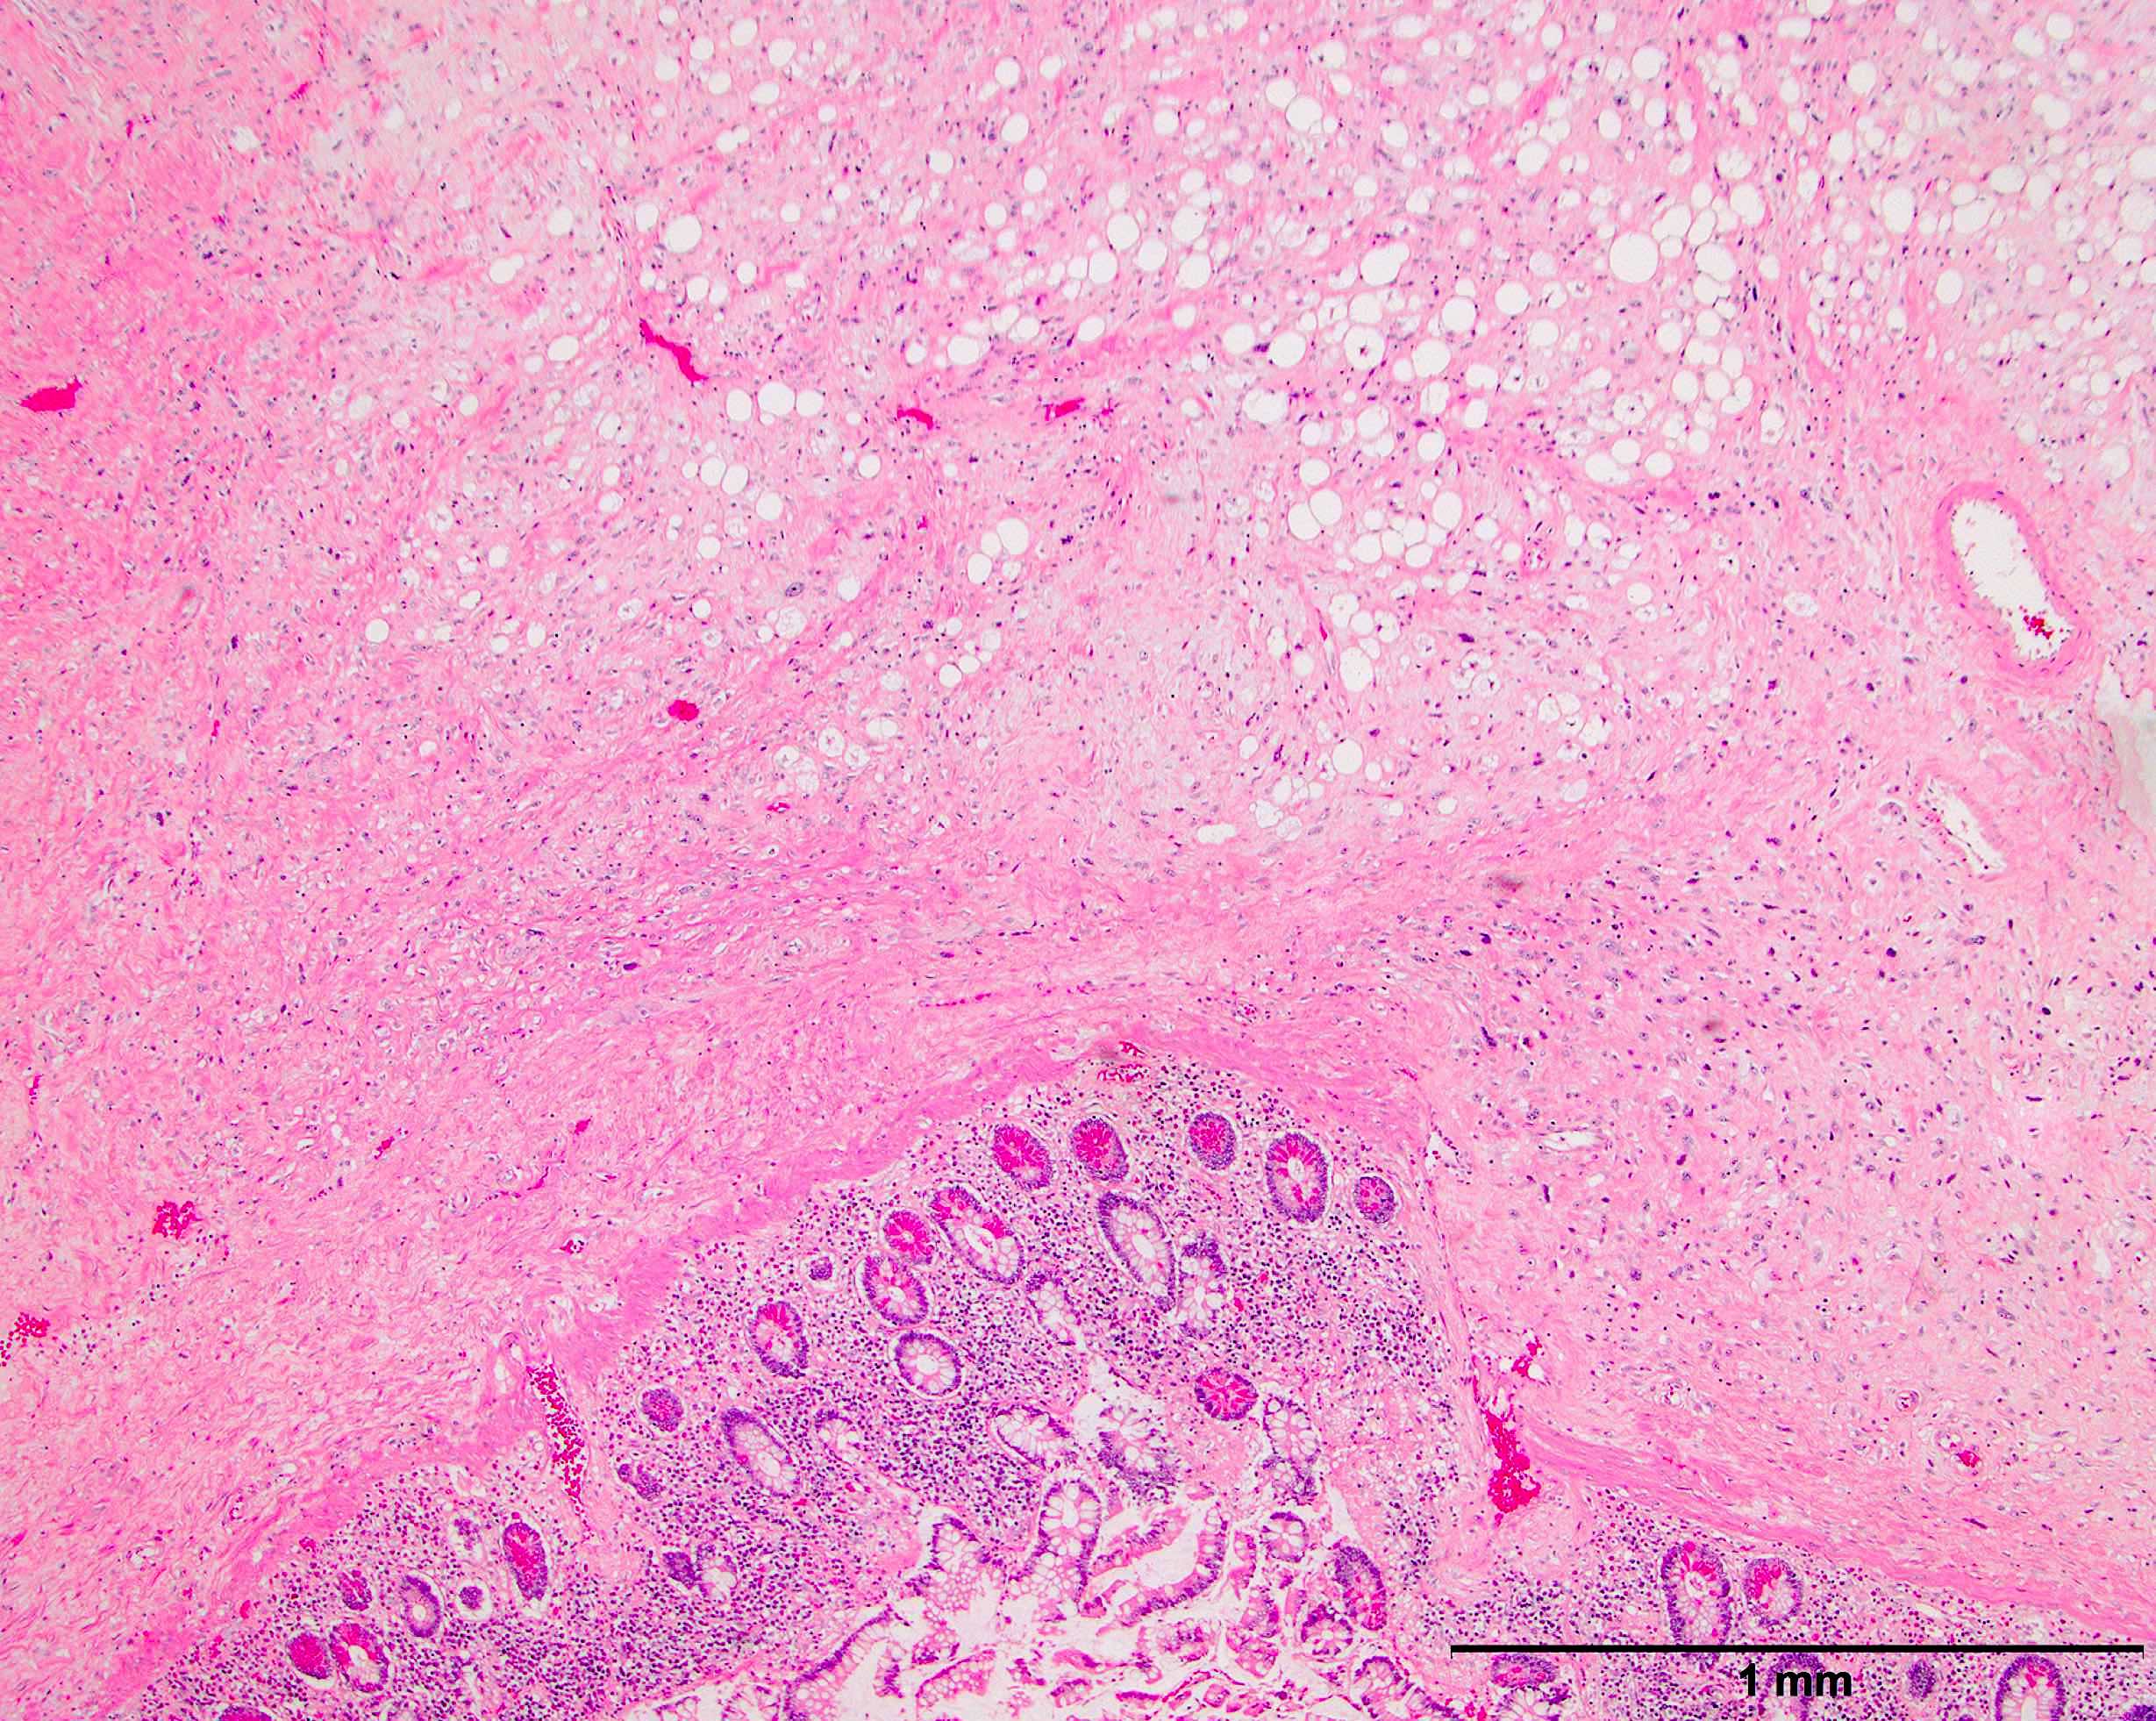

- High grade dedifferentiated liposarcoma

- Well differentiated and dedifferentiated components are often both present and can have abrupt or gradual transitions

- Dedifferentiated component is a cellular and typically a nonlipogenic sarcoma with significant pleomorphism

- Often resembles malignant fibrous histiocytoma (MFH), now referred to as undifferentiated pleomorphic sarcoma (UPS), with short fascicles of pleomorphic spindle cells associated with mixed inflammatory infiltrate

- Can show a peculiar whirling pattern reminiscent of meningothelial structures (Histopathology 1998;33:414, Am J Surg Pathol 1998;22:945)

- Low grade dedifferentiated liposarcoma

- Less common low grade tumor resembling fibromatosis or well differentiated fibrosarcoma

- Nonlipogenic (in contrast to well differentiated spindle cell liposarcoma, which contains atypical fat / lipoblasts)

- Look at the edges of dedifferentiated liposarcoma to identify a rim of background well differentiated liposarcoma that may mimic compressed background fat with reactive change

Microscopic (histologic) images

Contributed by Michael R. Clay, M.D. and AFIP

A 10 cm retroperitoneal mass was surgically resected with the histologic appearance shown in the image above. Which one of the following ancillary tests would best help support the diagnostic impression?

D. FISH positive for MDM2 gene amplification. The microscopic image demonstrates a proliferation of variably sized adipocytes admixed with scattered enlarged, hyperchromatic tumor cells that abruptly transitions to a cellular, spindle cell component with significant pleomorphism. These are the key histologic features of dedifferentiated liposarcoma. Detection of MDM2 amplification by FISH is a useful ancillary tool to confirm the diagnosis of both well differentiated and dedifferentiated liposarcoma. It is important to recognize, however, that MDM2 gene amplification is not entirely specific for well differentiated and dedifferentiated liposarcoma as it can also be found in other tumors, including intimal sarcoma, parosteal osteosarcoma, low grade central osteosarcoma, malignant peripheral nerve sheath tumor, endometrial stromal sarcoma and sclerosing rhabdomyosarcoma.